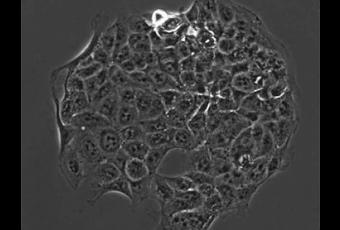

Les cellules de l'intérieur du corps humain sont généralement attachées grâce à un système structurel connu sous le nom de matrice extracellulaire via des protéines appelées intégrines, situées à la surface des cellules, qui constituent des points d'ancrage qui maintiennent les cellules en place. Lorsque les cellules cancéreuses métastasent, ces ancres se relâchent. En comparant, avec une nouvelle technologie, les propriétés d'adhérence de 4 stades de cellules cancéreuses, prélevées sur des souris génétiquement modifiées pour développer un cancer du poumon, les chercheurs ont pu identifier comment les cellules cancéreuses, à chaque stade de la tumeur, étaient fixées aux protéines de la matrice extracellulaire.

Source : Nature Communications doi:10.1038/ncomms2128 9 October 2012 A combinatorial extracellular matrix platform identifies cell-extracellular matrix interactions that correlate with metastasis(Visuel MIT @Nathan Reticker-Flynn « Une image microscopique des cellules cancéreuses qui adhèrent à un endroit recouvert de molécules dans la matrice extracellulaire »).